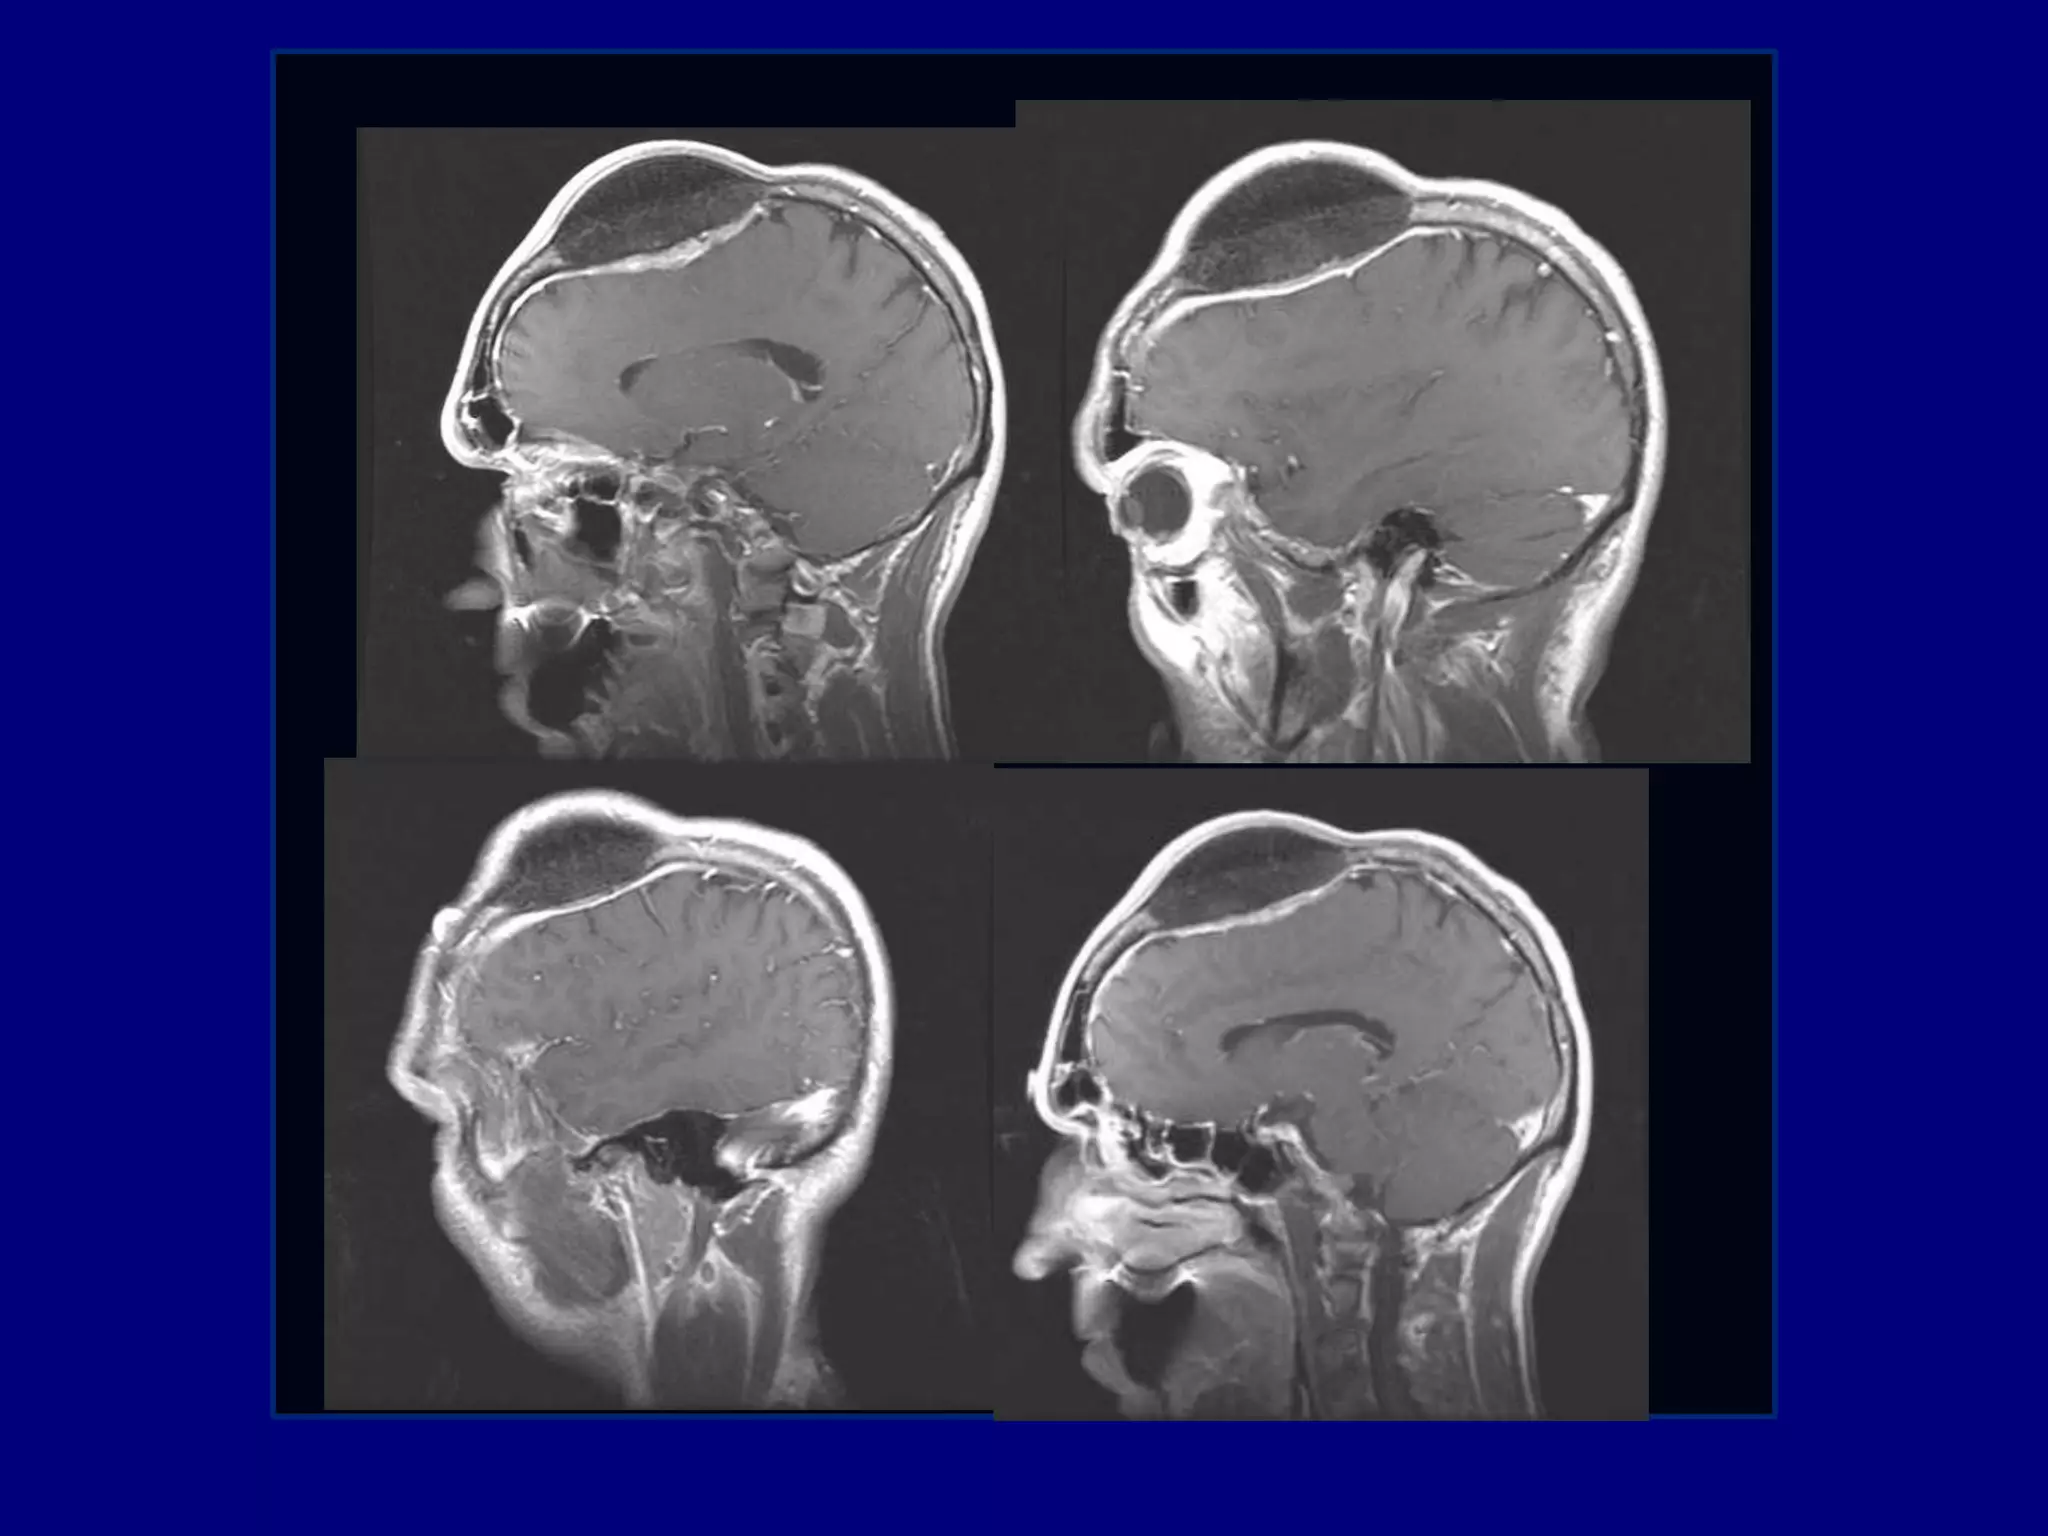

59-year-old male with the history of a slow

growing bony tumor of his right calvarium

The mass has grown over several years

No similar masses elsewhere

No associated neurological symptoms or pain

Medical consultation for cosmetic reasons

Computed Tomography

Magnetic Resonance Imaging

Post-gadolinium MPRAGE images for surgical planning